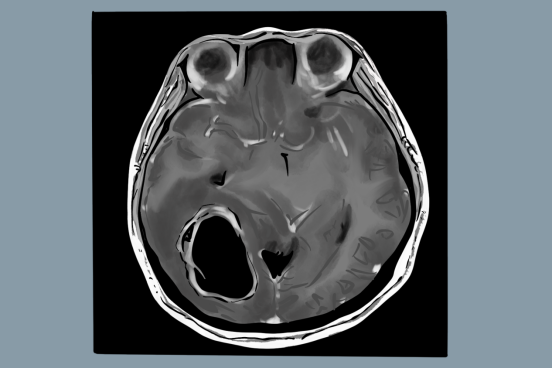

●CT或MRI检查提示有脑内占位性病变;

随着神经影像技术的进步,以DCE-MRI(磁共振动态增强)为代表的MRI影像组学,从脑胶质瘤的影像学特征、血流分布特点等多维度评价脑胶质瘤的恶性程度,为脑胶质瘤的术前分级和术后评价提供更加准确依据,也在一定程度上提高了脑胶质瘤的临床综合诊疗水平。